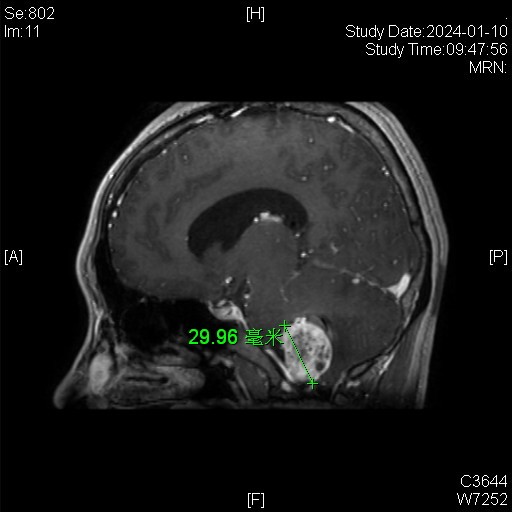

病例特点:

女性患者,26岁,因“间断性头晕1月余。”于2024-01-08入院。

患者1月余前感冒后出现头晕,伴头痛,伴恶心、呕吐。

家族史:患者母亲诊断多发小脑血管母细胞瘤,在我院手术治疗。

体检发现肝脏多发囊肿、右肾囊肿、胰腺多发囊肿。

诊断:延髓血管母细胞瘤

von Hippel-Lindau综合征